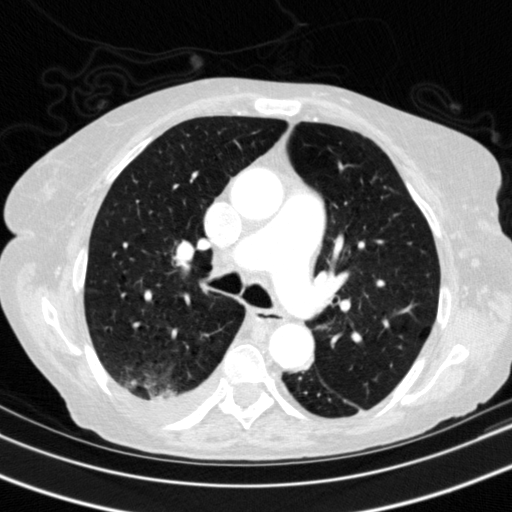

Original NATIVE CT scan (input)

Full window (WL 1023.5, WW 4095 β†’ Low βˆ’1024, High +3071)

Lung window (WL -600, WW 1500 β†’ Low βˆ’1350, High +150)